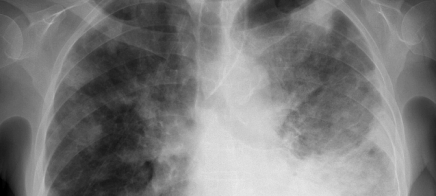

Unklare persistierende disseminierte Infiltrate der Lunge: Anamnese, Diagnostik und Therapie

Lernziel Anamnese, Klinik, logische Schritte zur Diagnose, Bildanalyse, Therapie.

Was dieser Kurs von Ihnen verlangt Auswahl von Differenzialdiagnosen, die sich im Therapieverlauf nicht eindeutig voneinander trennen lassen. Diagnostische Entscheidungen auch noch nach Wochen der eingeleiteten Therapie.